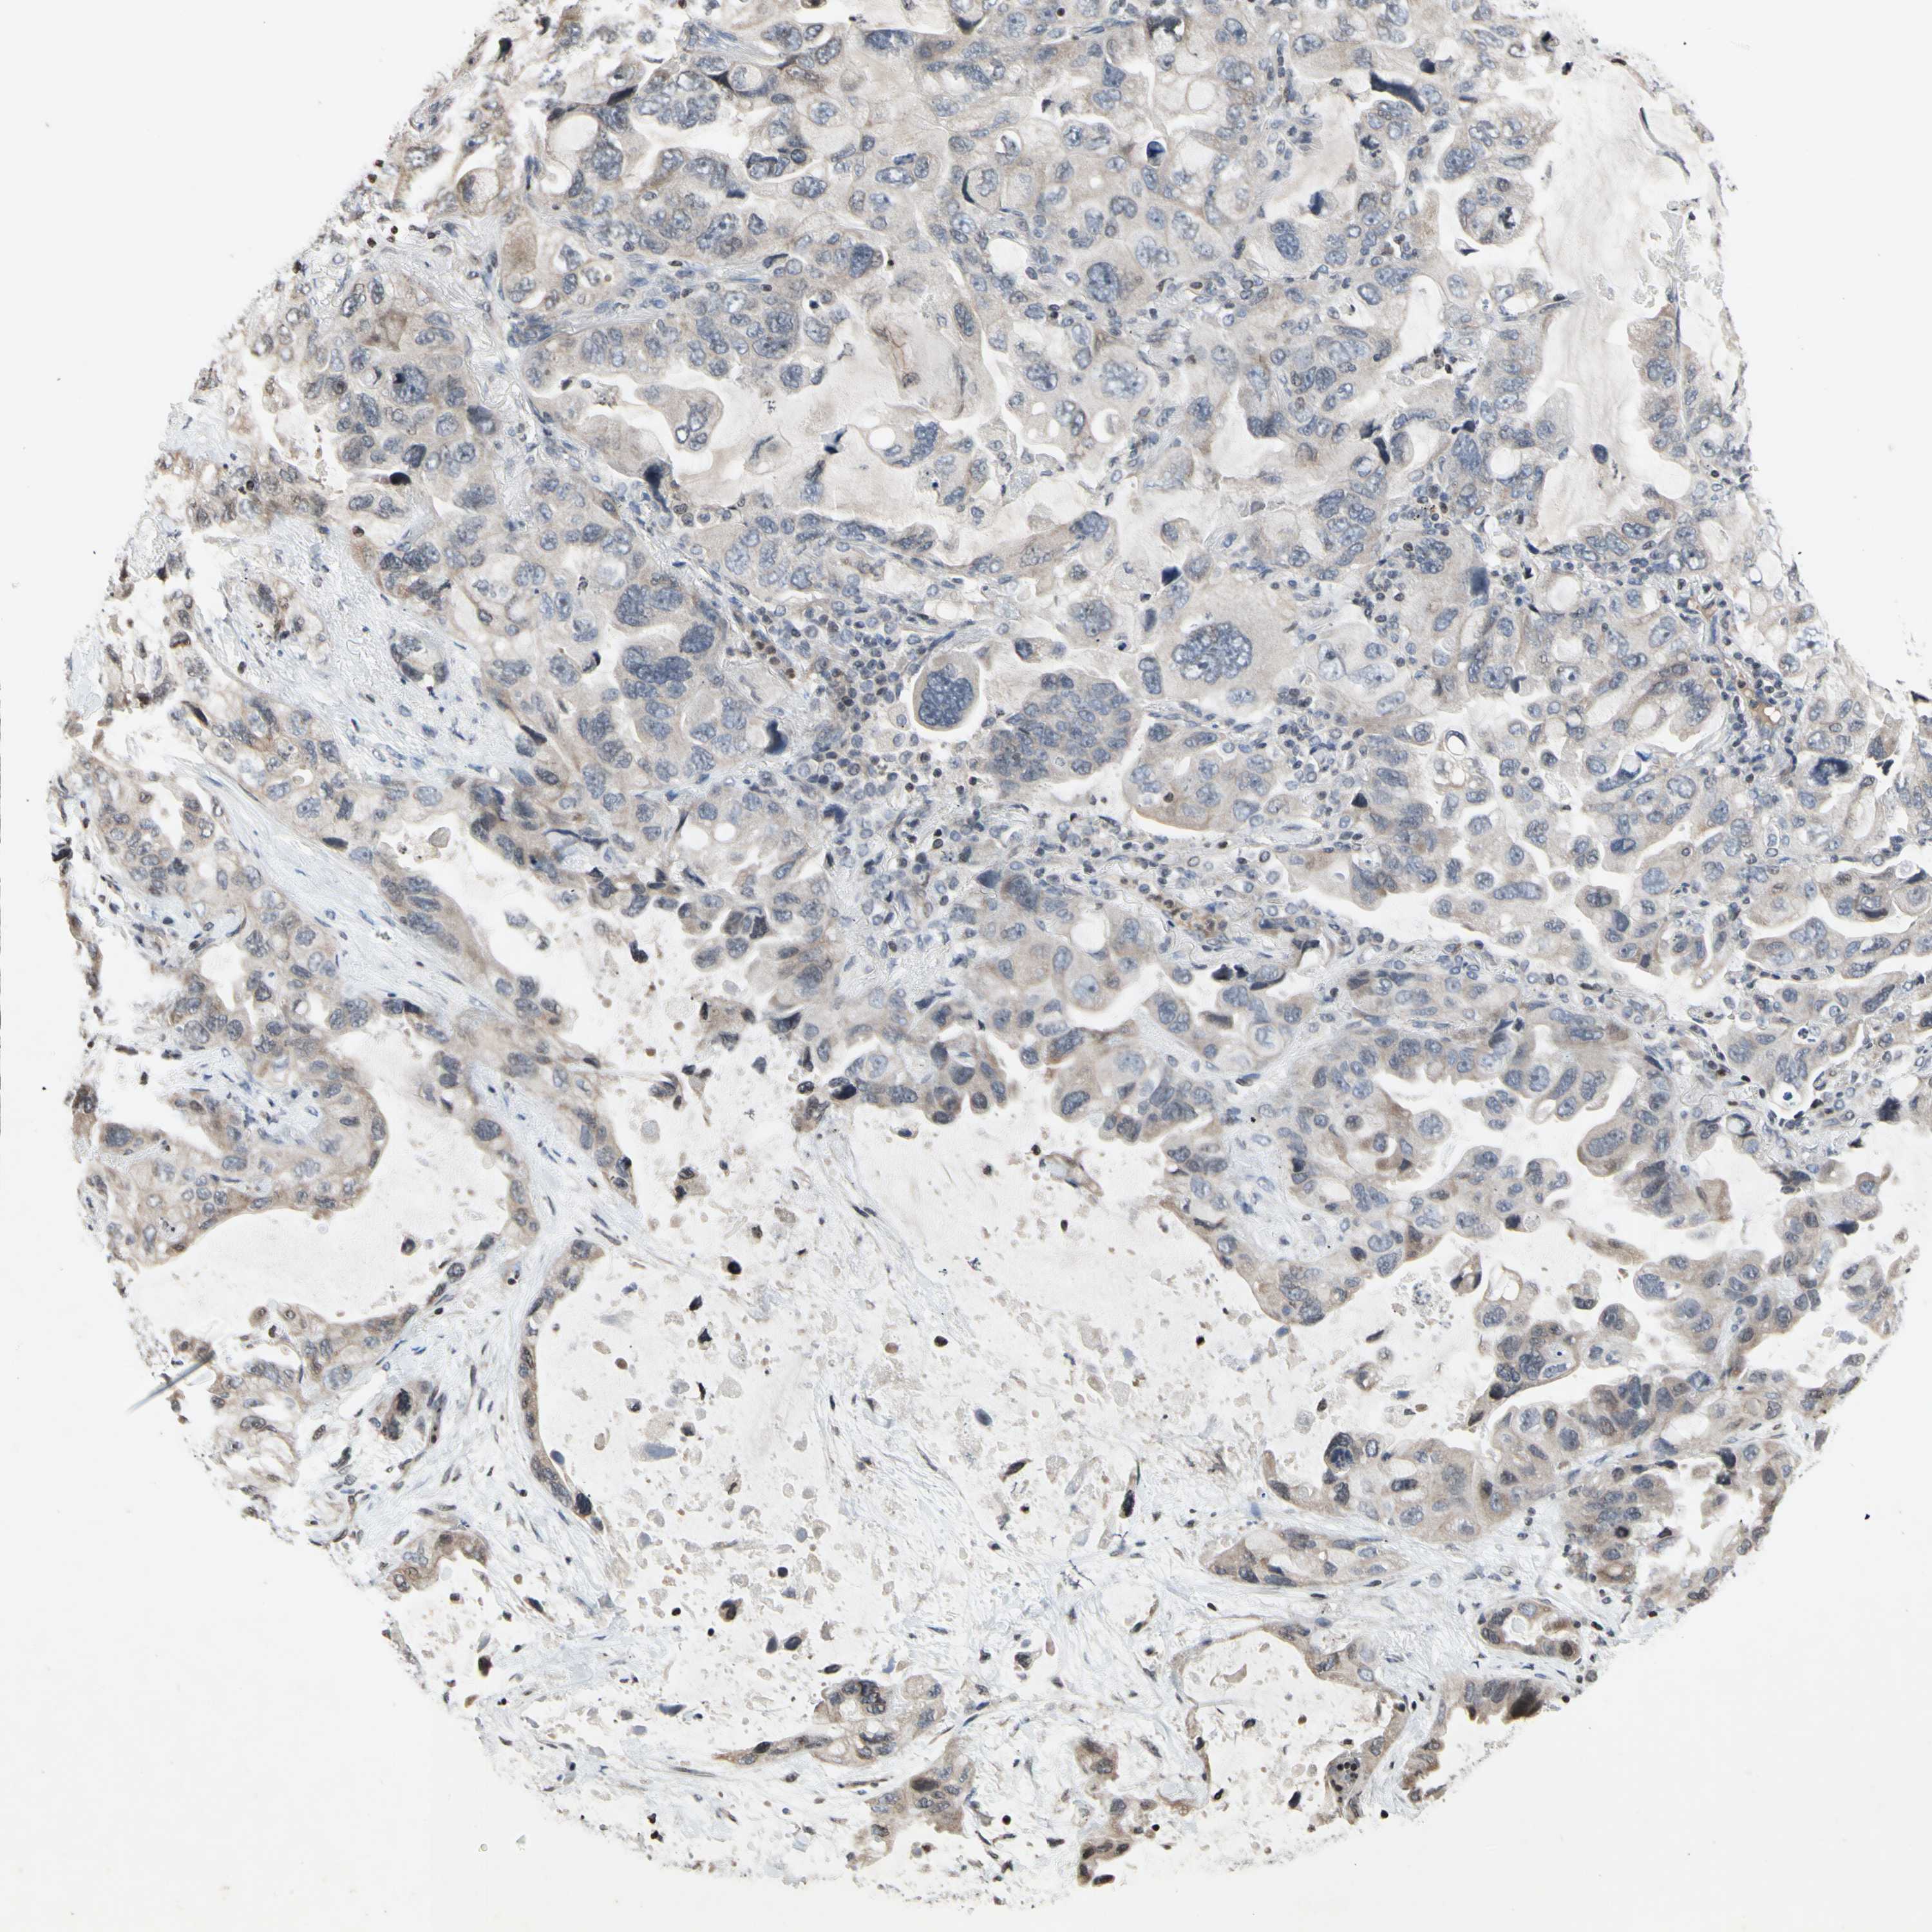

CANCER LUNG CANCER Show tissue menu

LUAD TCGA LUAD VALIDATION LUSC TCGA LUSC VALIDATION PROTEIN LUAD CPTAC PROTEIN LUSC CPTAC PROTEIN EXPRESSION

ANTIBODIES

AND

VALIDATION